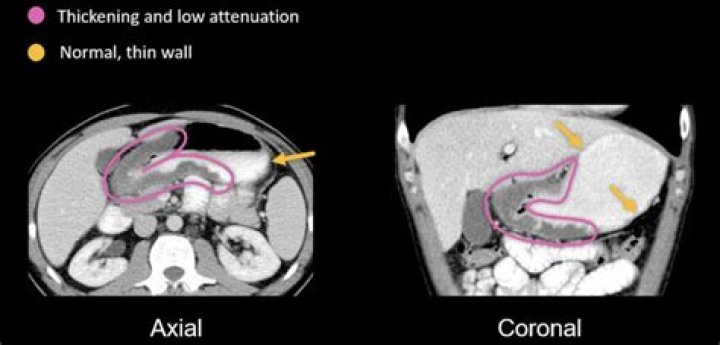

CT. Femoral hernias typically have a characteristic funnel-shaped neck. On axial CT images, the neck of the femoral hernia sac may be seen as a narrow protrusion through the femoral ring just medial to the common femoral vein. This can often look indented and compressed by the hernia sac.